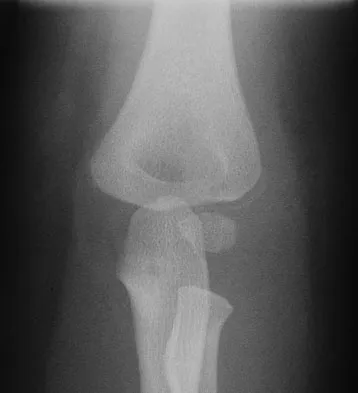

Figures 12a through 12e show the radiograph, MRI scans, and biopsy specimens of a 17-year-old boy. What is the most likely diagnosis?

The images show an epiphyseal lesion. The MRI scan shows extensive bone edema surrounding the lesion, consistent with chondroblastoma. Histology shows polygonal chondroblasts in a cobblestone-like pattern and areas of calcification consistent with chondroblastoma. Although some giant cells are seen, the age of the patient and the polygonal chondroblasts differentiate this lesion from giant cell tumor. Clear cell chondrosarcoma is an epiphyseal lesion that occurs in an older population, and the cells have clear cytoplasm. This lesion is not producing bone on imaging or histologic specimen, eliminating osteosarcoma. Tuberculous septic arthritis can be an epiphyseal lesion, but granulomas would be seen on histology. Menendez LR (ed): Orthopaedic Knowledge Update: Musculoskeletal Tumors. Rosemont, IL, American Academy of Orthopaedic Surgeons, 2002, pp 103-111.